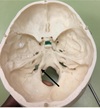

1. Identify the spaces labelled.

Anterior Cranial Fossa, Middle Cranial Fossa, Posterior Cranial Fossa

120

1. Identify the structure. 2. What are the subdivisions of this structure? 3. What structures traverse these subdivisions?

1. Jugular Foramen, CN 9,10, 11 2. Anterior Intermediate, posterior 3. The anterior compartment transmits the inferior petrosal sinus and glossopharyngeal nerve (CN IX) The intermediate transmits the vagus and accessory nerves (aka cranial nerves number X, and XI respectively). The posterior transmits the sigmoid sinus (becoming the internal jugular vein) and some meningeal branches from the occipital and ascending pharyngeal arteries.

121

1. Identify the canal. 2. What structures traverse this canal?

1. Hypoglossal canal 2. Hypoglossal Nerve

122

1. Formaen Magnum 2. Spinal cord, CN11 accessory, vertebral arteries.

123